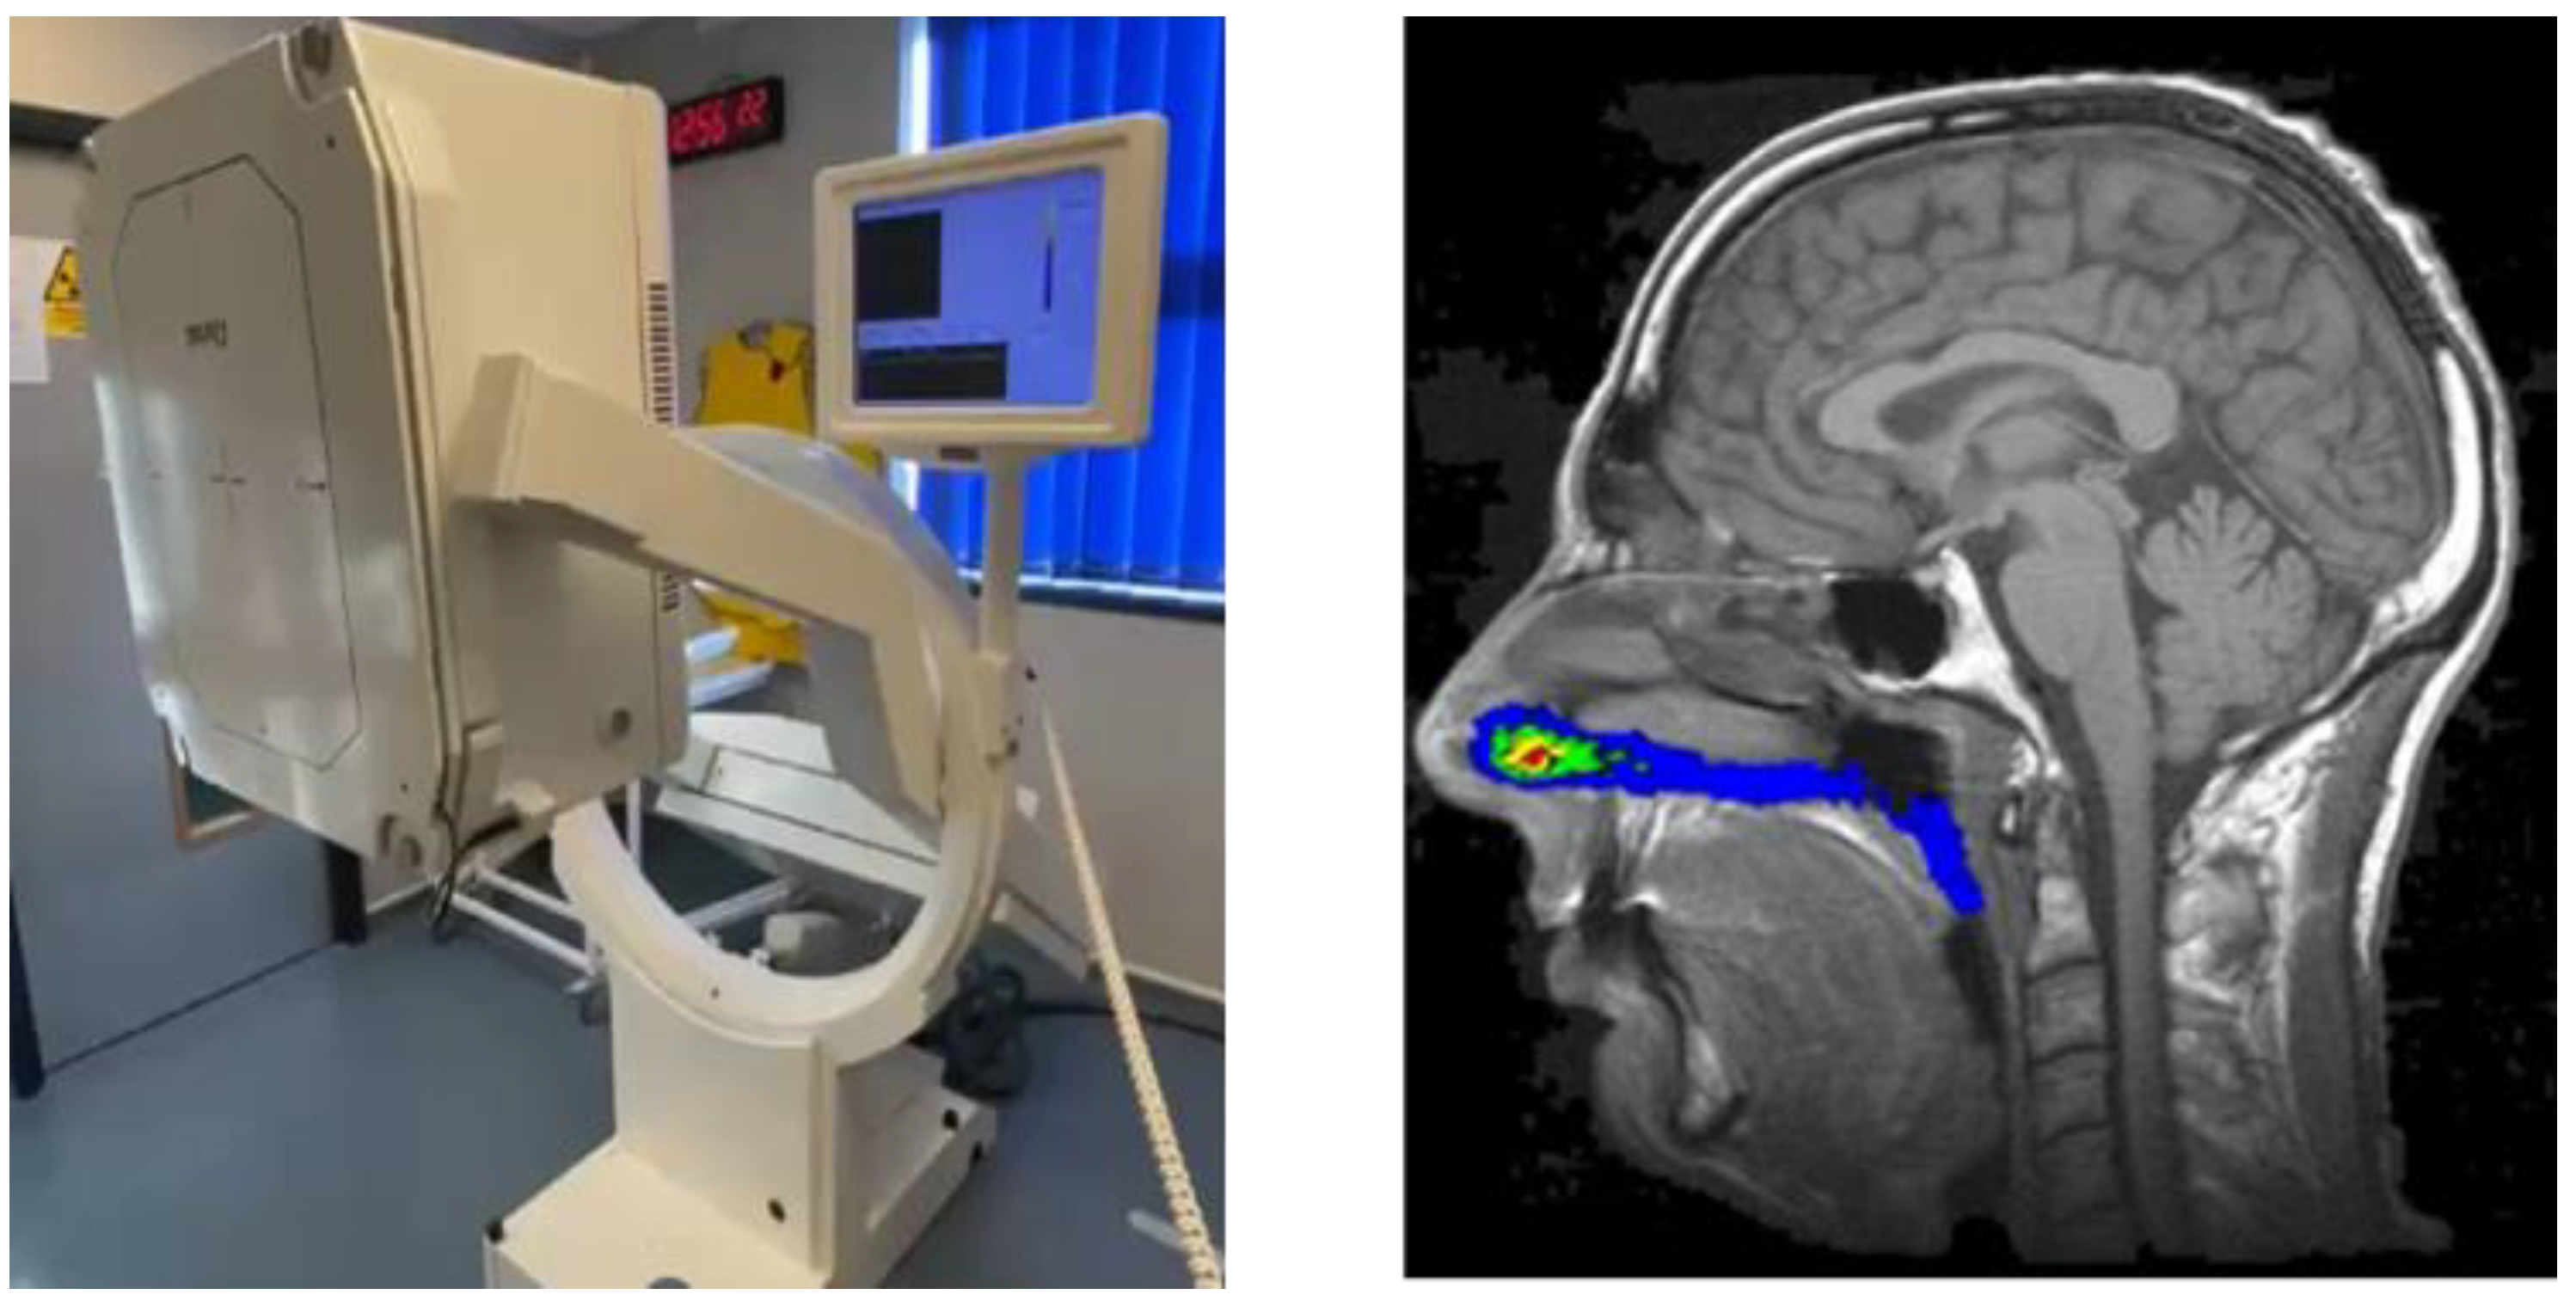

6.1. Gamma Scintigraphy

- Newman, S.P.; Illum, L. Radionuclide imaging studies in the assessment of nasal drug delivery in humans. Am. J. Drug Deliv. 2004, 2, 101–112. [Google Scholar] [CrossRef]

- Shah, S.A.; Berger, R.L.; McDermott, J.; Gupta, P.; Monteith, D.; Connor, A.; Lin, W. Regional deposition of mometasone furoate nasal spray suspension in humans. Allergy Asthma Proc. 2015, 36, 48–57. [Google Scholar] [CrossRef] [PubMed]

- Yamada, K.; Ishii, K.; Newman, S. Optimization of Nasal Dosing Regimens for Olfactory Delivery. In Proceedings of the Controlled Release Society (CRS), Copenhagen, Denmark, 18–22 July 2009. [Google Scholar]